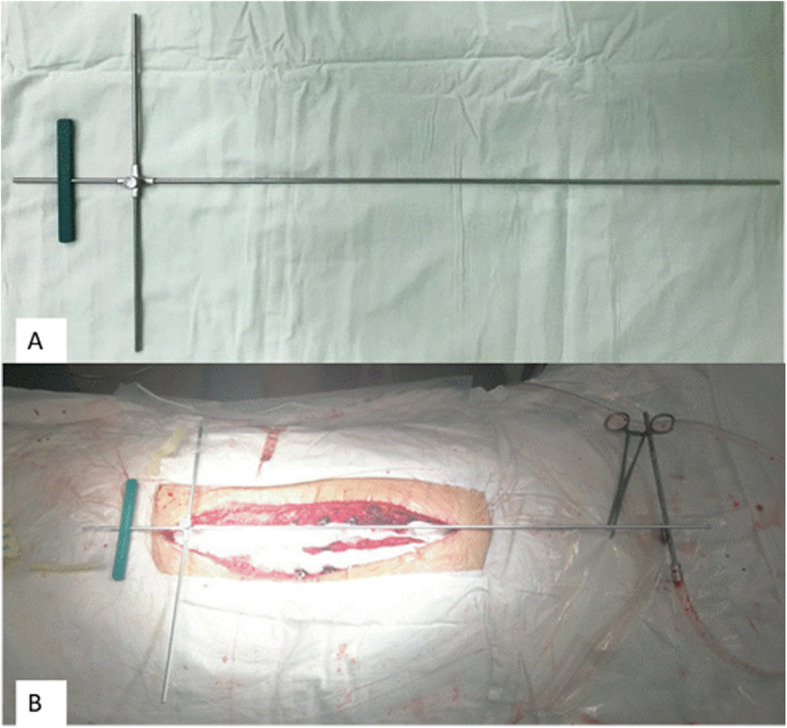

IGCA consists of 2 parts: (1), lower body part aligner: it is an imaginary line made up of physical surface landmarks of lower body part such as the midpoints between two symmetrical heels/ankles/knees, passing through gluteal cleft, this line overlaps CSVL (Fig. 1a); and (2), upper body part aligner, which is served by an inverted cross device. This device is composed of one shorter vertical limb, one longer vertical limb and two horizontal limbs of equal length (Fig. 2a), the green plastic bar is a scaled marker, which makes the shorter vertical limb overlay CSVL more easily intraoperatively. The longer vertical limb is telescoped, which can slide inward or outward depending on patient’s height. When the shorter vertical limb overlays CSVL, ideally, the longer vertical limb would pass across C7 center.

The inverted cross device was used at the final steps of the instrumentation. After the deformity was initially corrected, the inverted cross device was to be aligned on a patient (Fig. 2b). Its horizontal limbs were placed on the pelvis to align with supra-iliac line and shorter vertical limb in line with CSVL by using C arm. The longer vertical limb was then imaged fluoroscopically to check if it passed through C7 body (Fig. 3a). If it did, a well-balanced body would be obtained (Fig. 3b); If it did not, further maneuvers such as in situ coronal bending of the rods, compression, and distraction were performed to improve spinal deformity correction until C7 body was crossed.